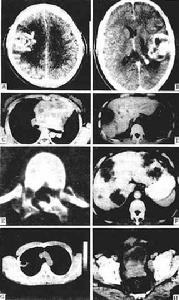

6.腦CT檢查CT對顱內腫瘤特別是幕上腫瘤的診斷,比其它輔助診斷技術有更多的優點是較為理想的檢查診斷方法。